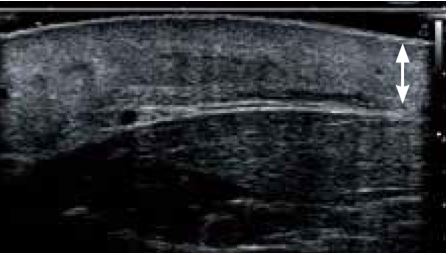

Злоякісна меланома

а) Сірошкальне зображення

б) Зображення cSMI

Малюнок 3. Злоякісна меланома, отримана за допомогою PLI-2004BX (24 МГц).